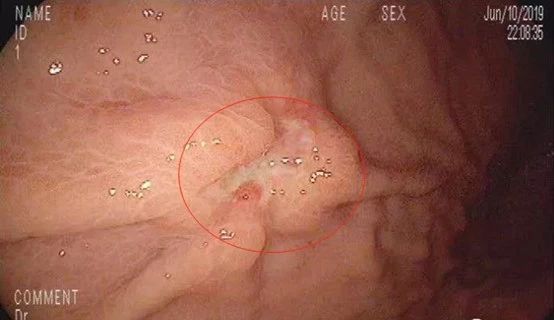

随后充分充气,胃腔皱襞完全展开,果然在胃体中部大弯侧近前壁发现一处隆起凹陷型溃疡病变,大小约2x1.5cm,看起来,这就不是什么好东西!

上午9:30,胃镜下病灶处深部取材8块,准备送检做病理检查。

2019年6月14日,活检结果出来了,病理诊断:低分化印戒细胞癌!